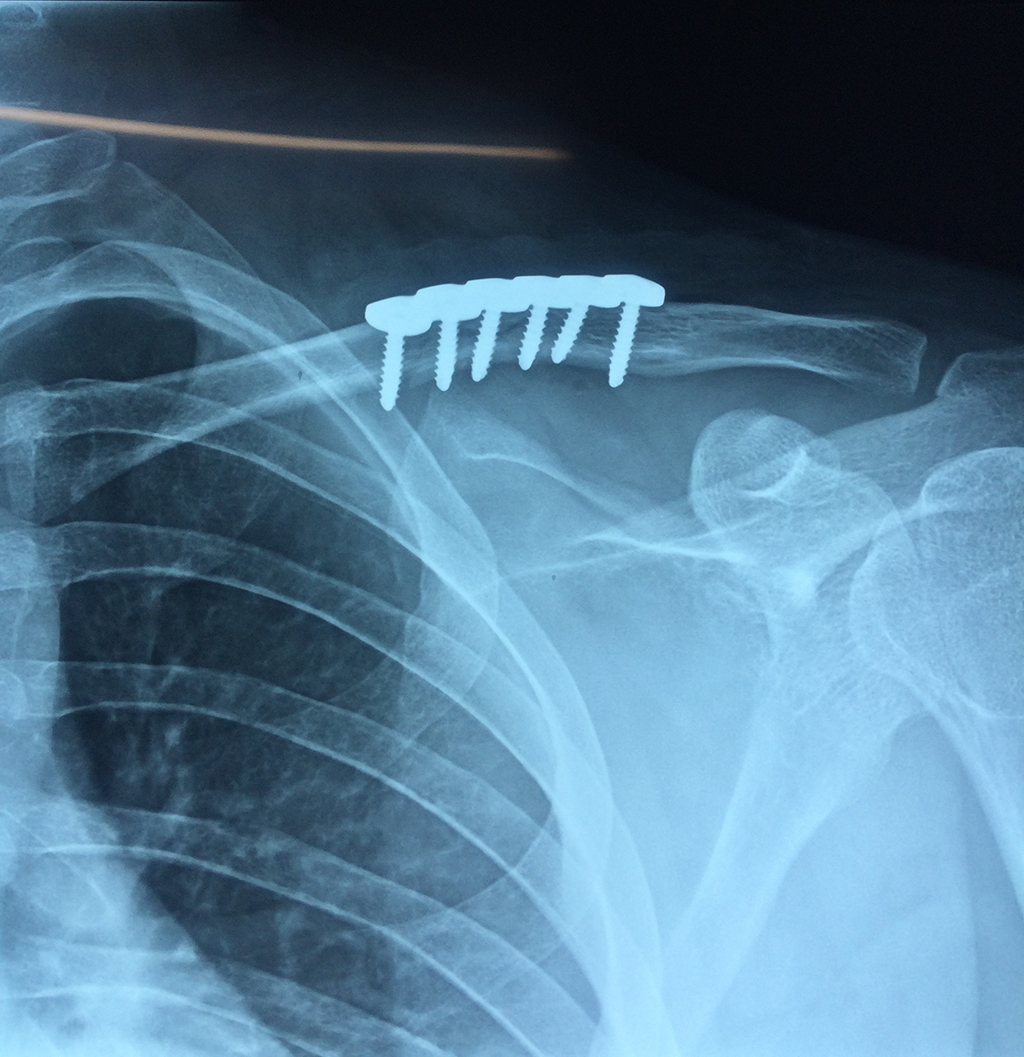

Cirugías de Hombros - Clavícula

La clavícula es un hueso largo, con forma de "S" itálica, situado en la parte anterosuperior del tórax. Junto con la escápula forman la cintura escapular. Se puede palpar por toda su longitud y se extiende del esternón al acromion de la escápula, siguiendo una dirección oblicua lateral y posterior.